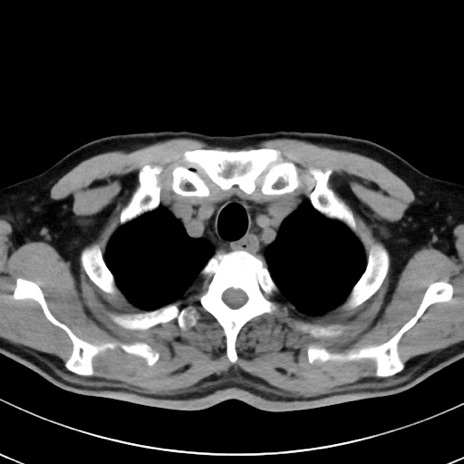

【腹部TIPS】症例29 参考症例 CT(横断像)

症例

70歳代男性